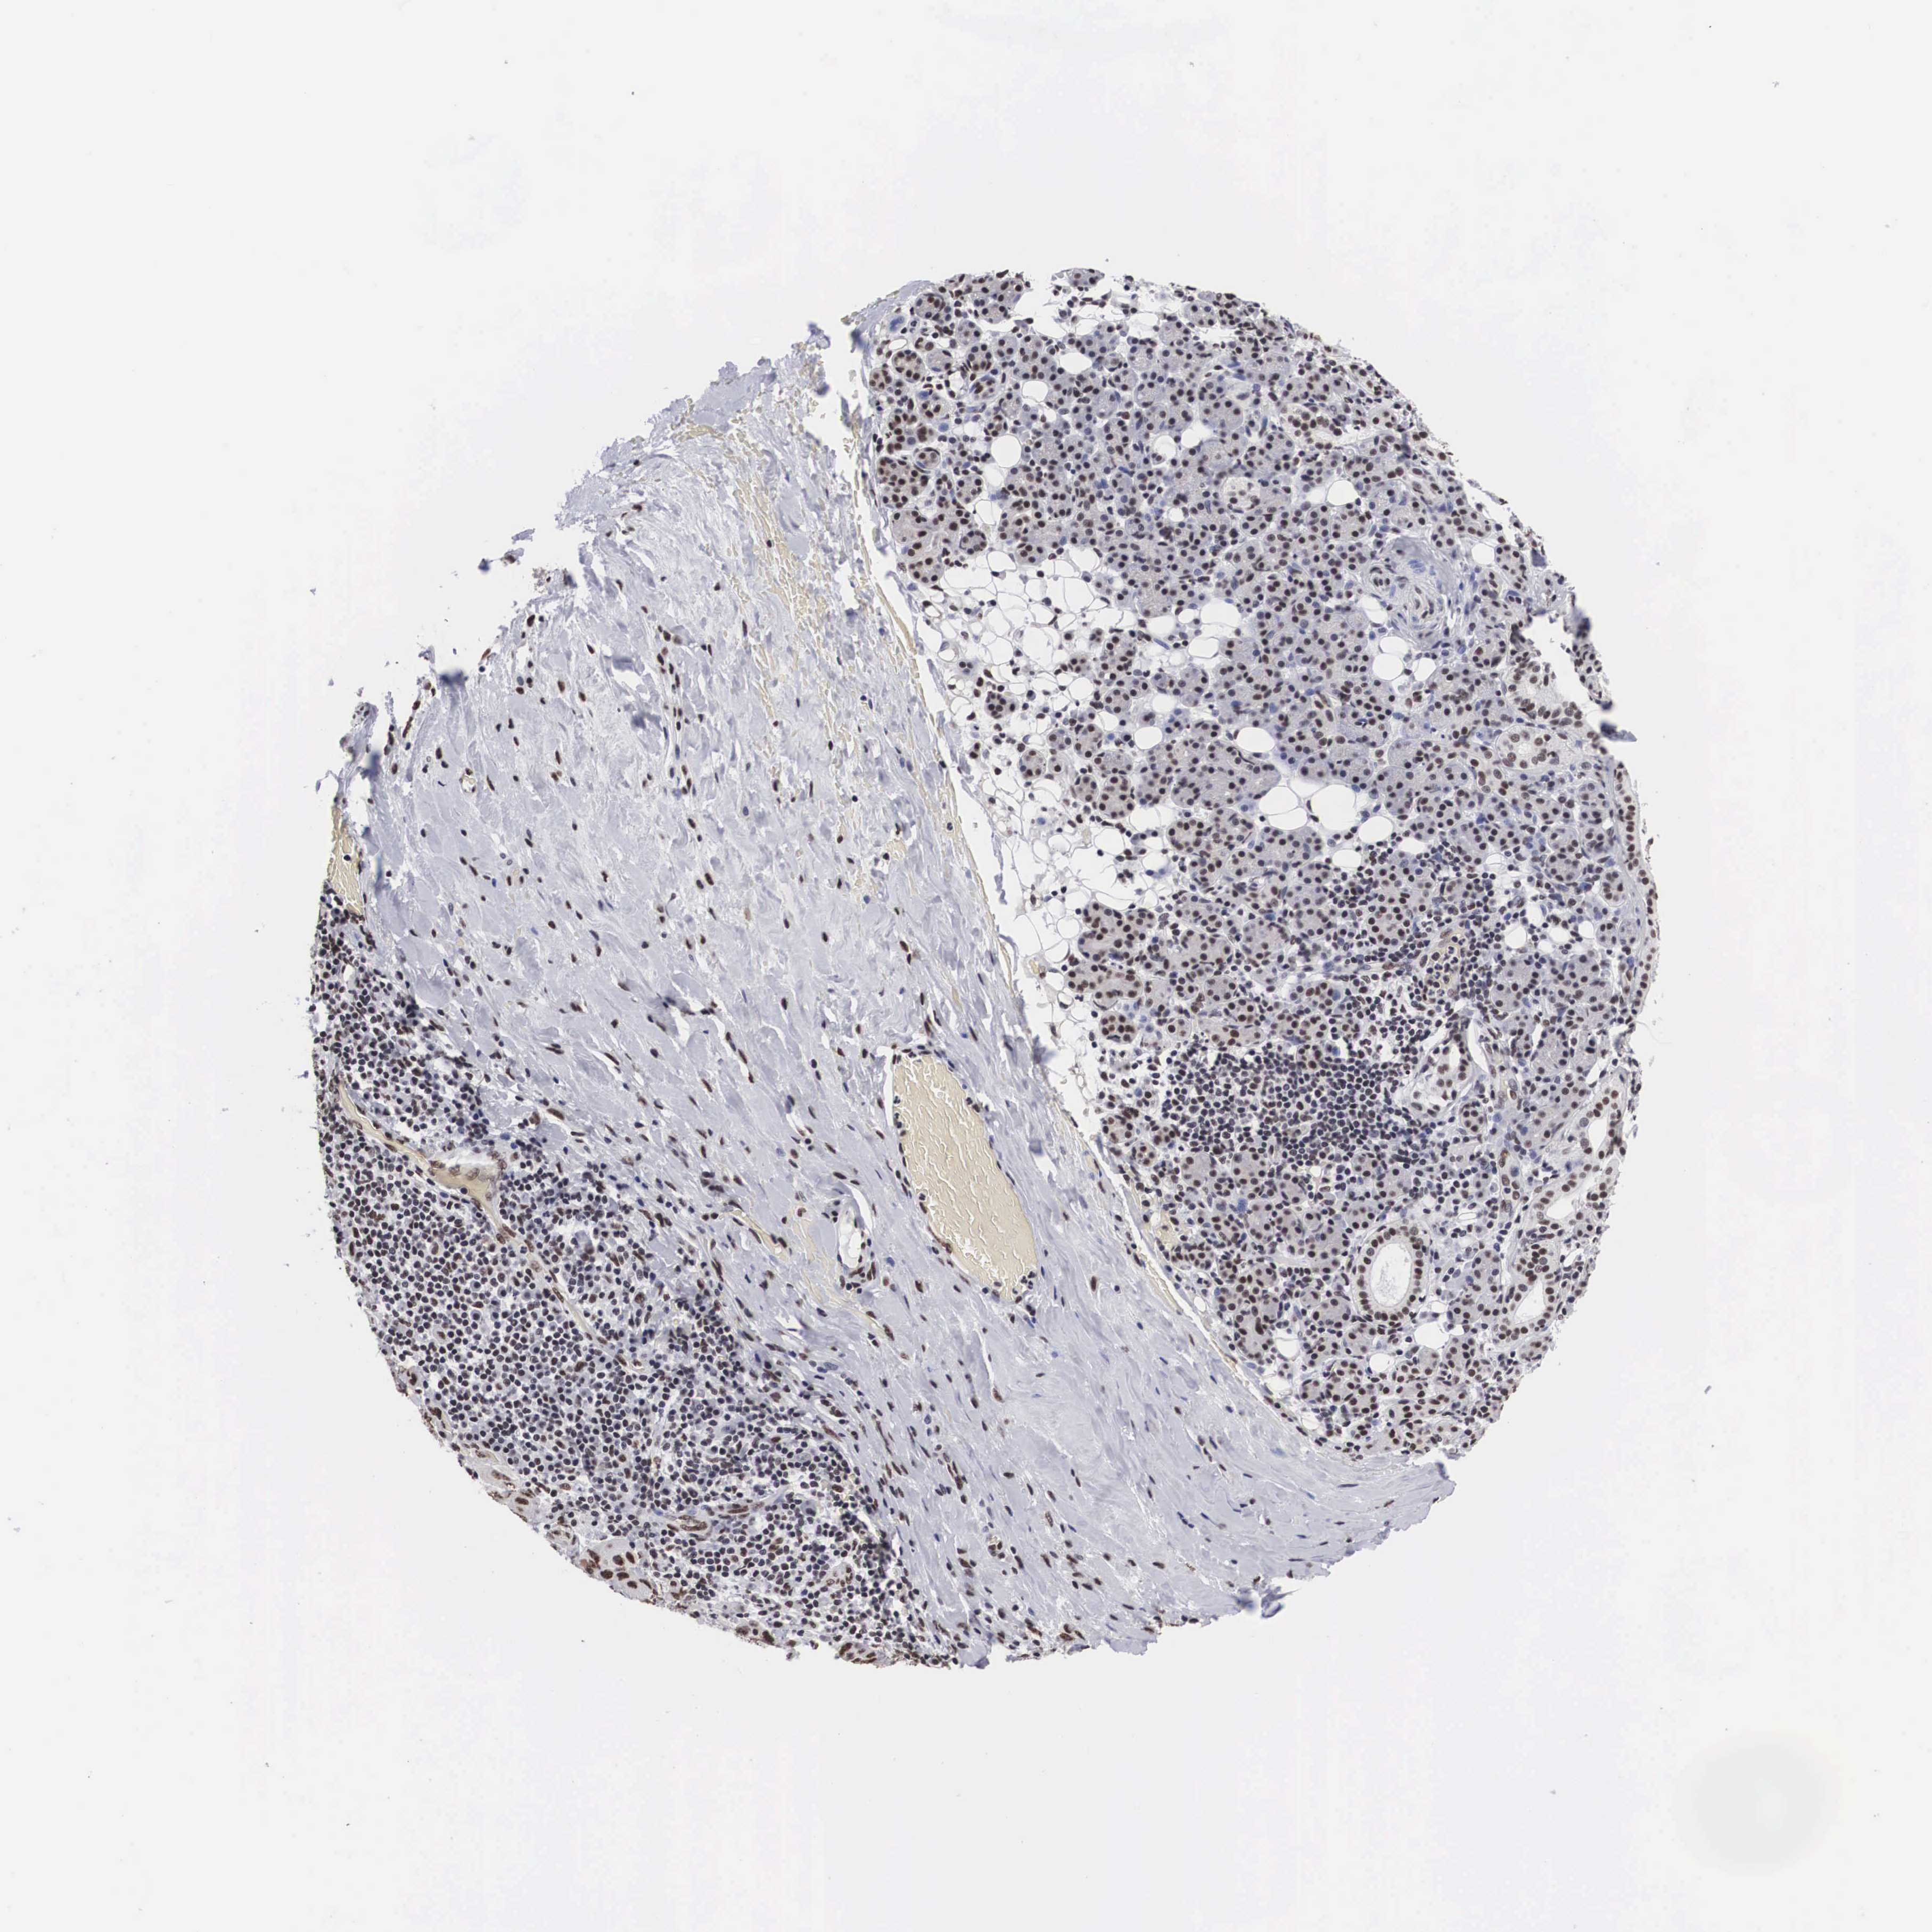

SKIN CANCER - Protein expressioni

A mouse-over function shows sample information and annotation data. Click on an image to view it in a full screen mode. Samples can be filtered based on level of antibody staining by selecting one or several of the following categories: high, medium, low and not detected. The assay and annotation is described here.

Antibody stainingi

Antibody staining in the annotated cell types in the current human tissue is reported as not detected, low, medium, or high, based on conventional immunohistochemistry profiling in selected tissues. This score is based on the combination of the staining intensity and fraction of stained cells.

Each image is clickable and will lead to virtual microscopy that enables deeper exploration of all samples and also displays staining intensity scores, fraction scores and subcellular localization as well as patient and tissue information for each sample.

Antibody HPA000657

Staining

High

Medium

Low

Not detected

Intensity

Strong

Moderate

Weak

Negative

Quantity

>75%

75%-25%

<25%

None

Location

Nuclear

Cytoplasmic/membranous

Cytoplasmic/membranous,nuclear

Squamous cell carcinoma, NOS

Basal cell carcinoma